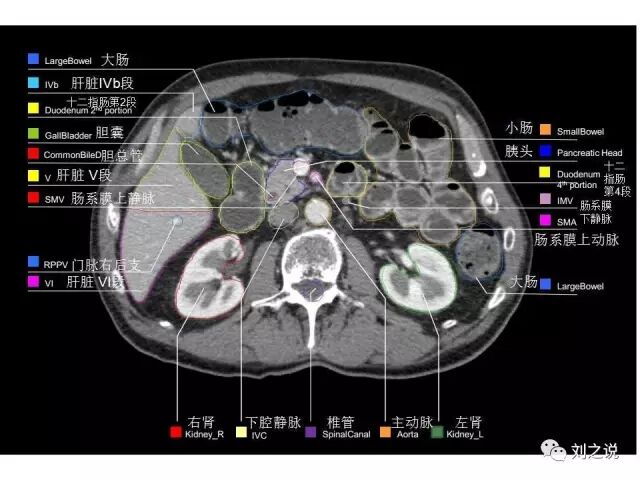

参考RTOG共识和3D-body解剖。

来源:刘之说